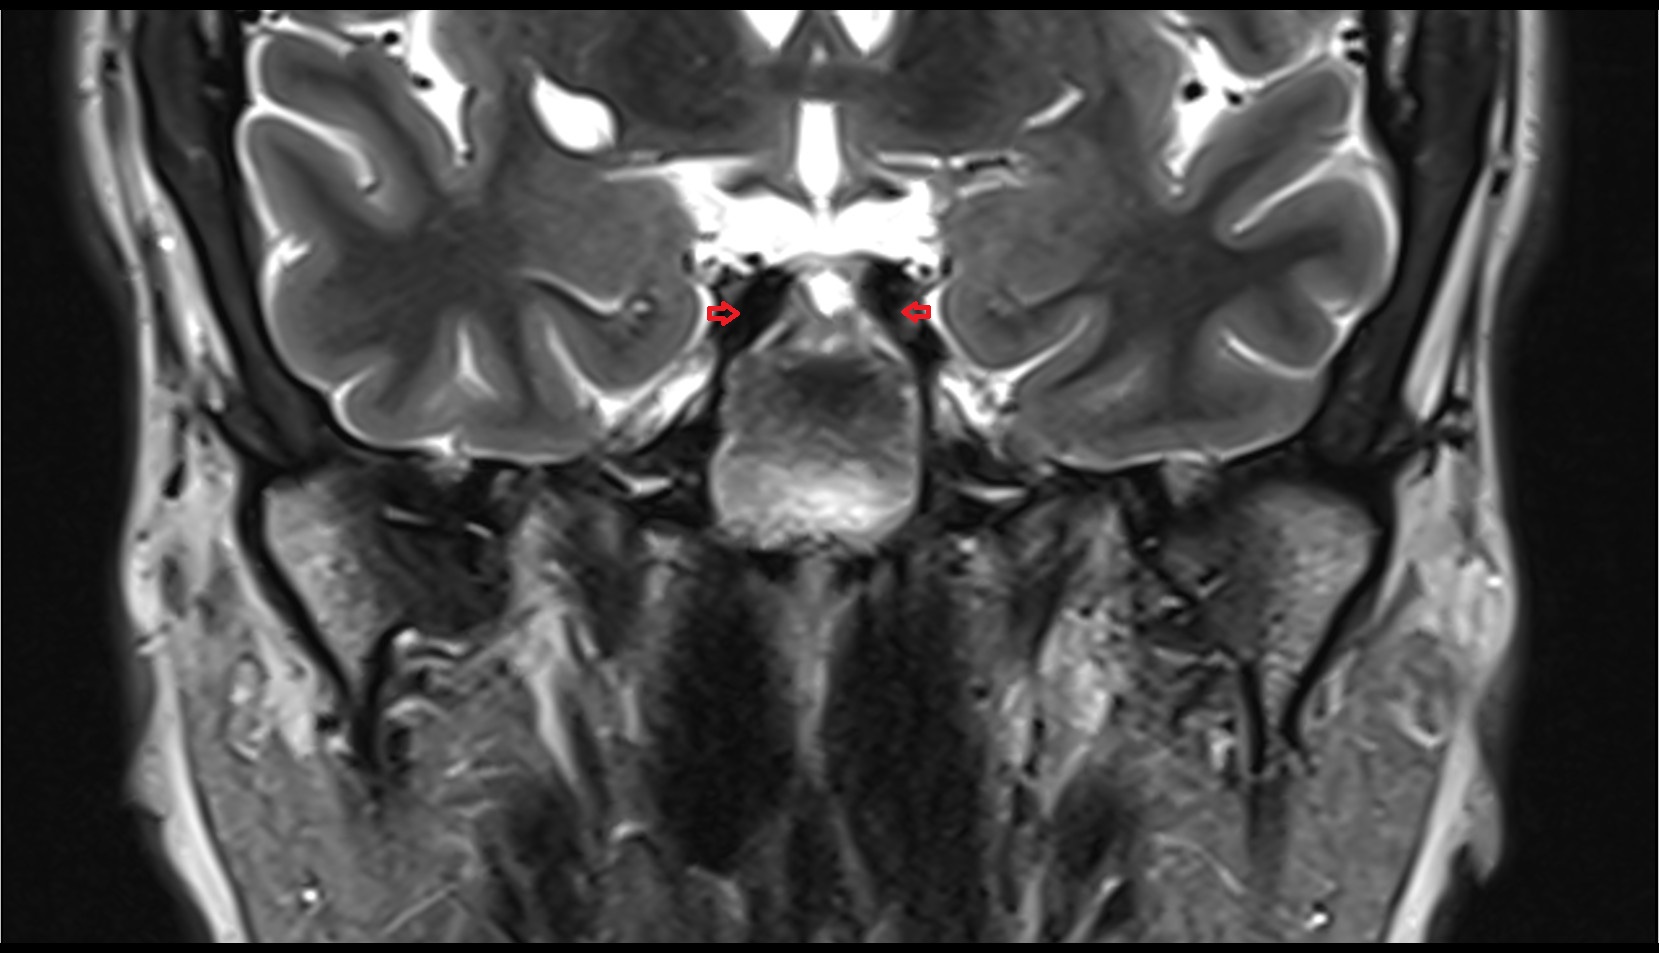

- Hippocampus